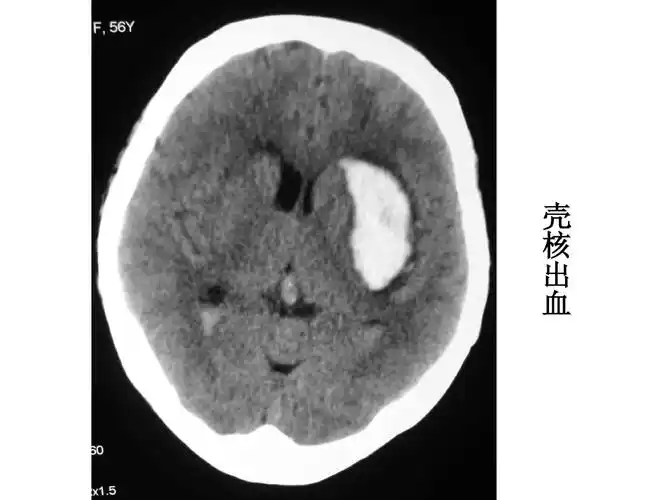

值班必备 | 急诊颅脑ct常见的八种疾病

图6. 2017年5月15日头颅ct显示脑沟脑池不清晰,脑肿胀明显.

影像总结头颅ct基本知识与常见病变